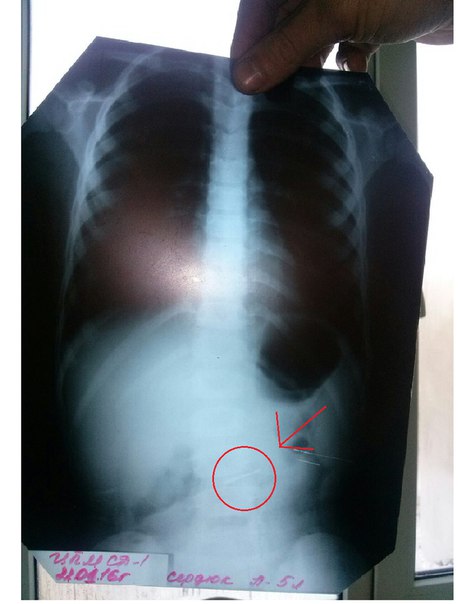

Мы уже сообщали о ЧП, произошедшем в государственной стоматологии. Родители сообщили, что после лечения зуба у ребенка в желудке оказался бур небольшого размера.